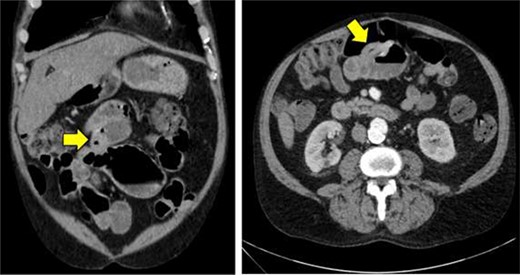

A 62-year-old man presented to the emergency room complaining of progressive fatigue, weakness and black stools for 7 days. The patient denied any unintended weight loss, night sweats, headaches, rectal bleeding, bloody stools, hematemesis or other related symptoms. His medical history was significant for a previous hemorrhagic stroke without any neurological deficits as well as an open abdominal aortic repair, and he had no family history of malignancy. Physical exam was largely unremarkable. The patient was afebrile, hemodynamically stable, and his abdomen was soft and non-tender with no palpable masses. Similarly, rectal exam did not reveal any obvious pathology, though hemoccult test was positive. Laboratory studies revealed a hemoglobin of 7.1 g/dl (normal range 13.5–17.5 g/dl) with mean corpuscular volume of 75.9 fl (normal range 80–100 fl), consistent with a microcytic anemia. A subsequent computed tomography angiogram of the abdomen and pelvis was performed, which was only significant for mild thickening of the wall of the proximal ileum (Fig. 1).

Computed tomography imaging of the abdomen and pelvis showing mild thickening of the wall of the proximal ileum.